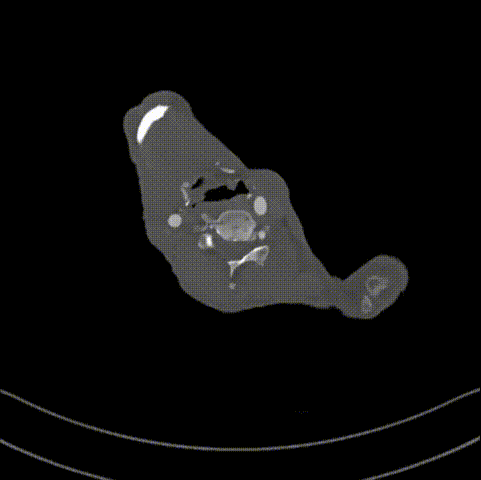

术前CTA详解

CTA提示患者主动脉弓型为Ⅲ型弓,左侧椎动脉为优势动脉,夹层累及至双侧髂外动脉,腹腔干动脉,肠系膜上动脉及左肾动脉为真腔供血,右肾动脉为真假腔供血,左侧胸腔少量积液。

降主段明显破口